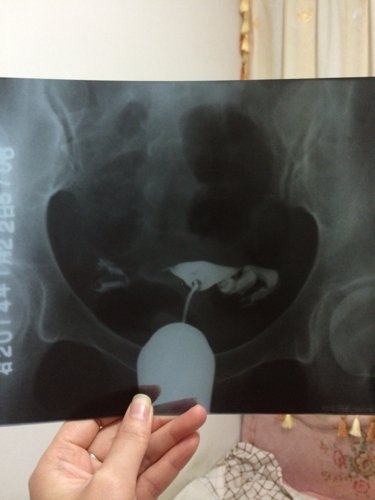

输卵管造影显示结果是左侧输卵管通而极不畅,壶腹部显示扩张,右侧输卵管不完全梗阻,有什么好的治疗方法

输卵管造影显示结果是左侧输卵管通而极不畅,壶腹部显示扩张,右侧输卵管不完全梗阻,有什么好的治疗方法吗?急急!

病情分析: 你好,你的情况不排除左侧输卵管壶腹部有积水的可能。 指导意见: 建议你可以服用中药治疗,同时配合灌肠治疗效果比较好的;也可以做腹腔镜手术治疗的。